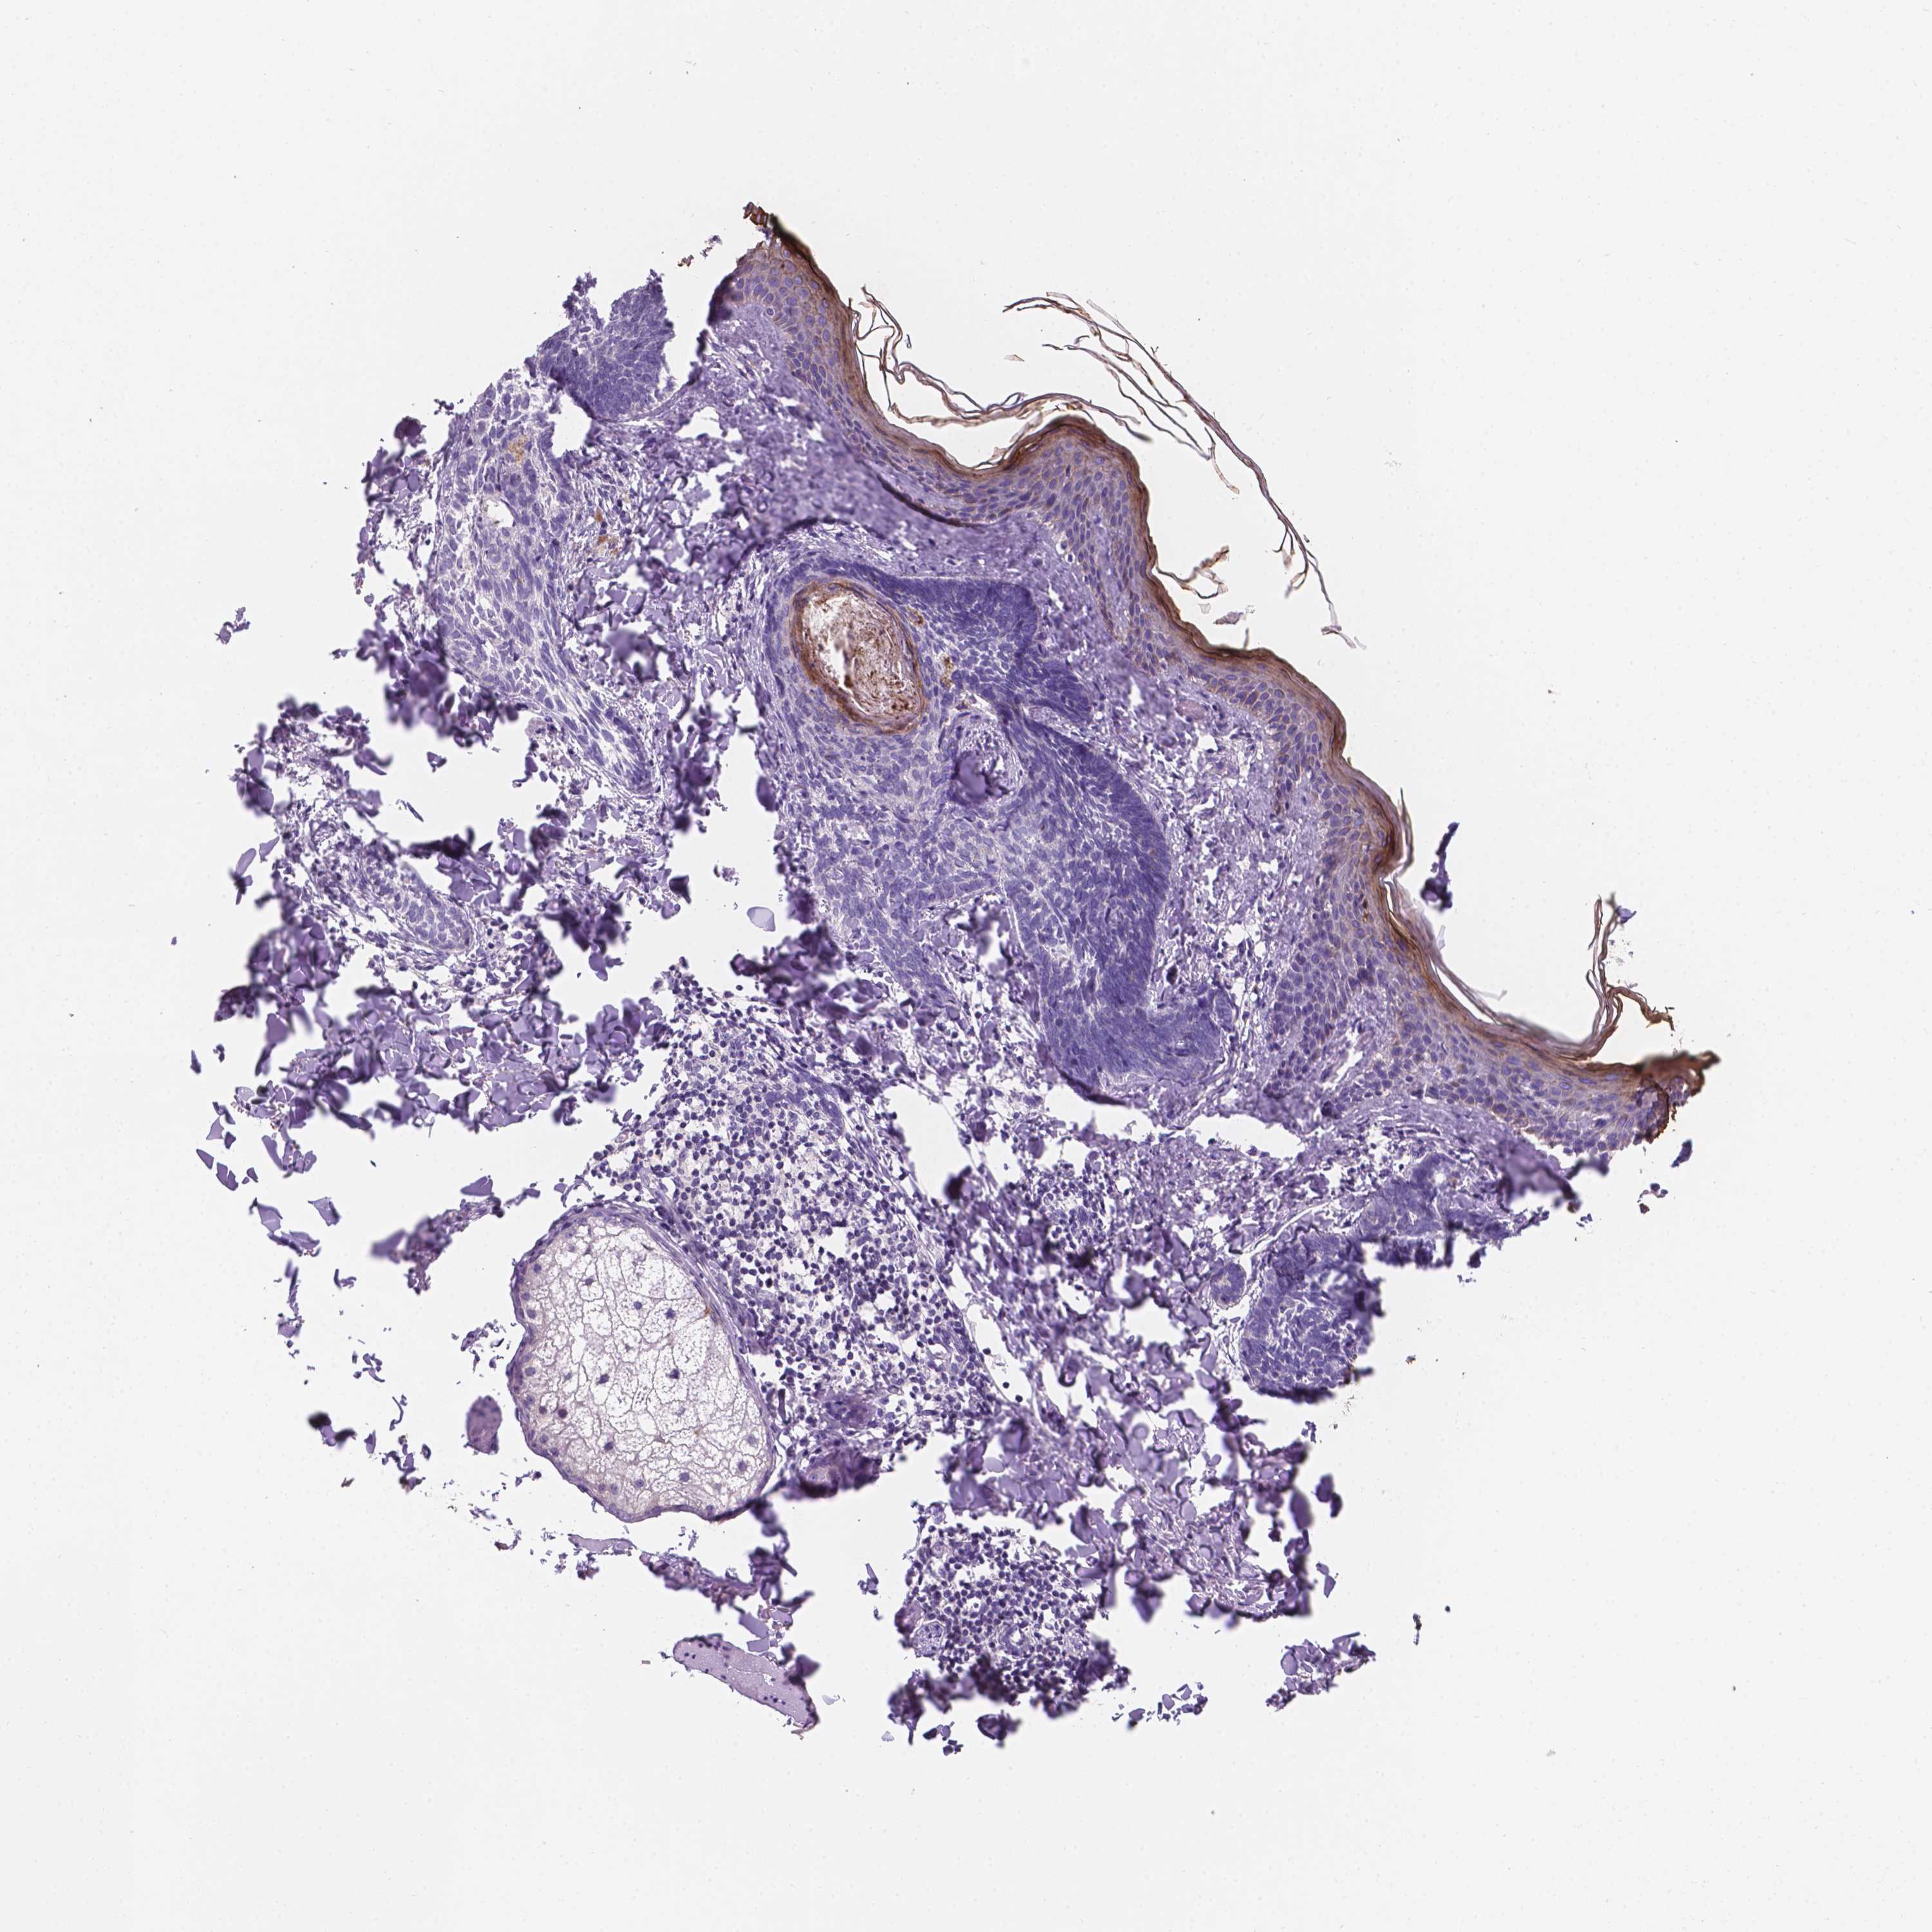

CANCER SKIN CANCER Show tissue menu

Basal cell and squamous cell cancer

SKIN CANCER - Protein expressioni

A mouse-over function shows sample information and annotation data. Click on an image to view it in a full screen mode. Samples can be filtered based on level of antibody staining by selecting one or several of the following categories: high, medium, low and not detected. The assay and annotation is described here.

Each image is clickable and will lead to virtual microscopy that enables deeper exploration of all samples and also displays staining intensity scores, fraction scores and subcellular localization as well as patient and tissue information for each sample.

Antibody HPA062568

Basal cell carcinoma

Squamous cell carcinoma, NOS